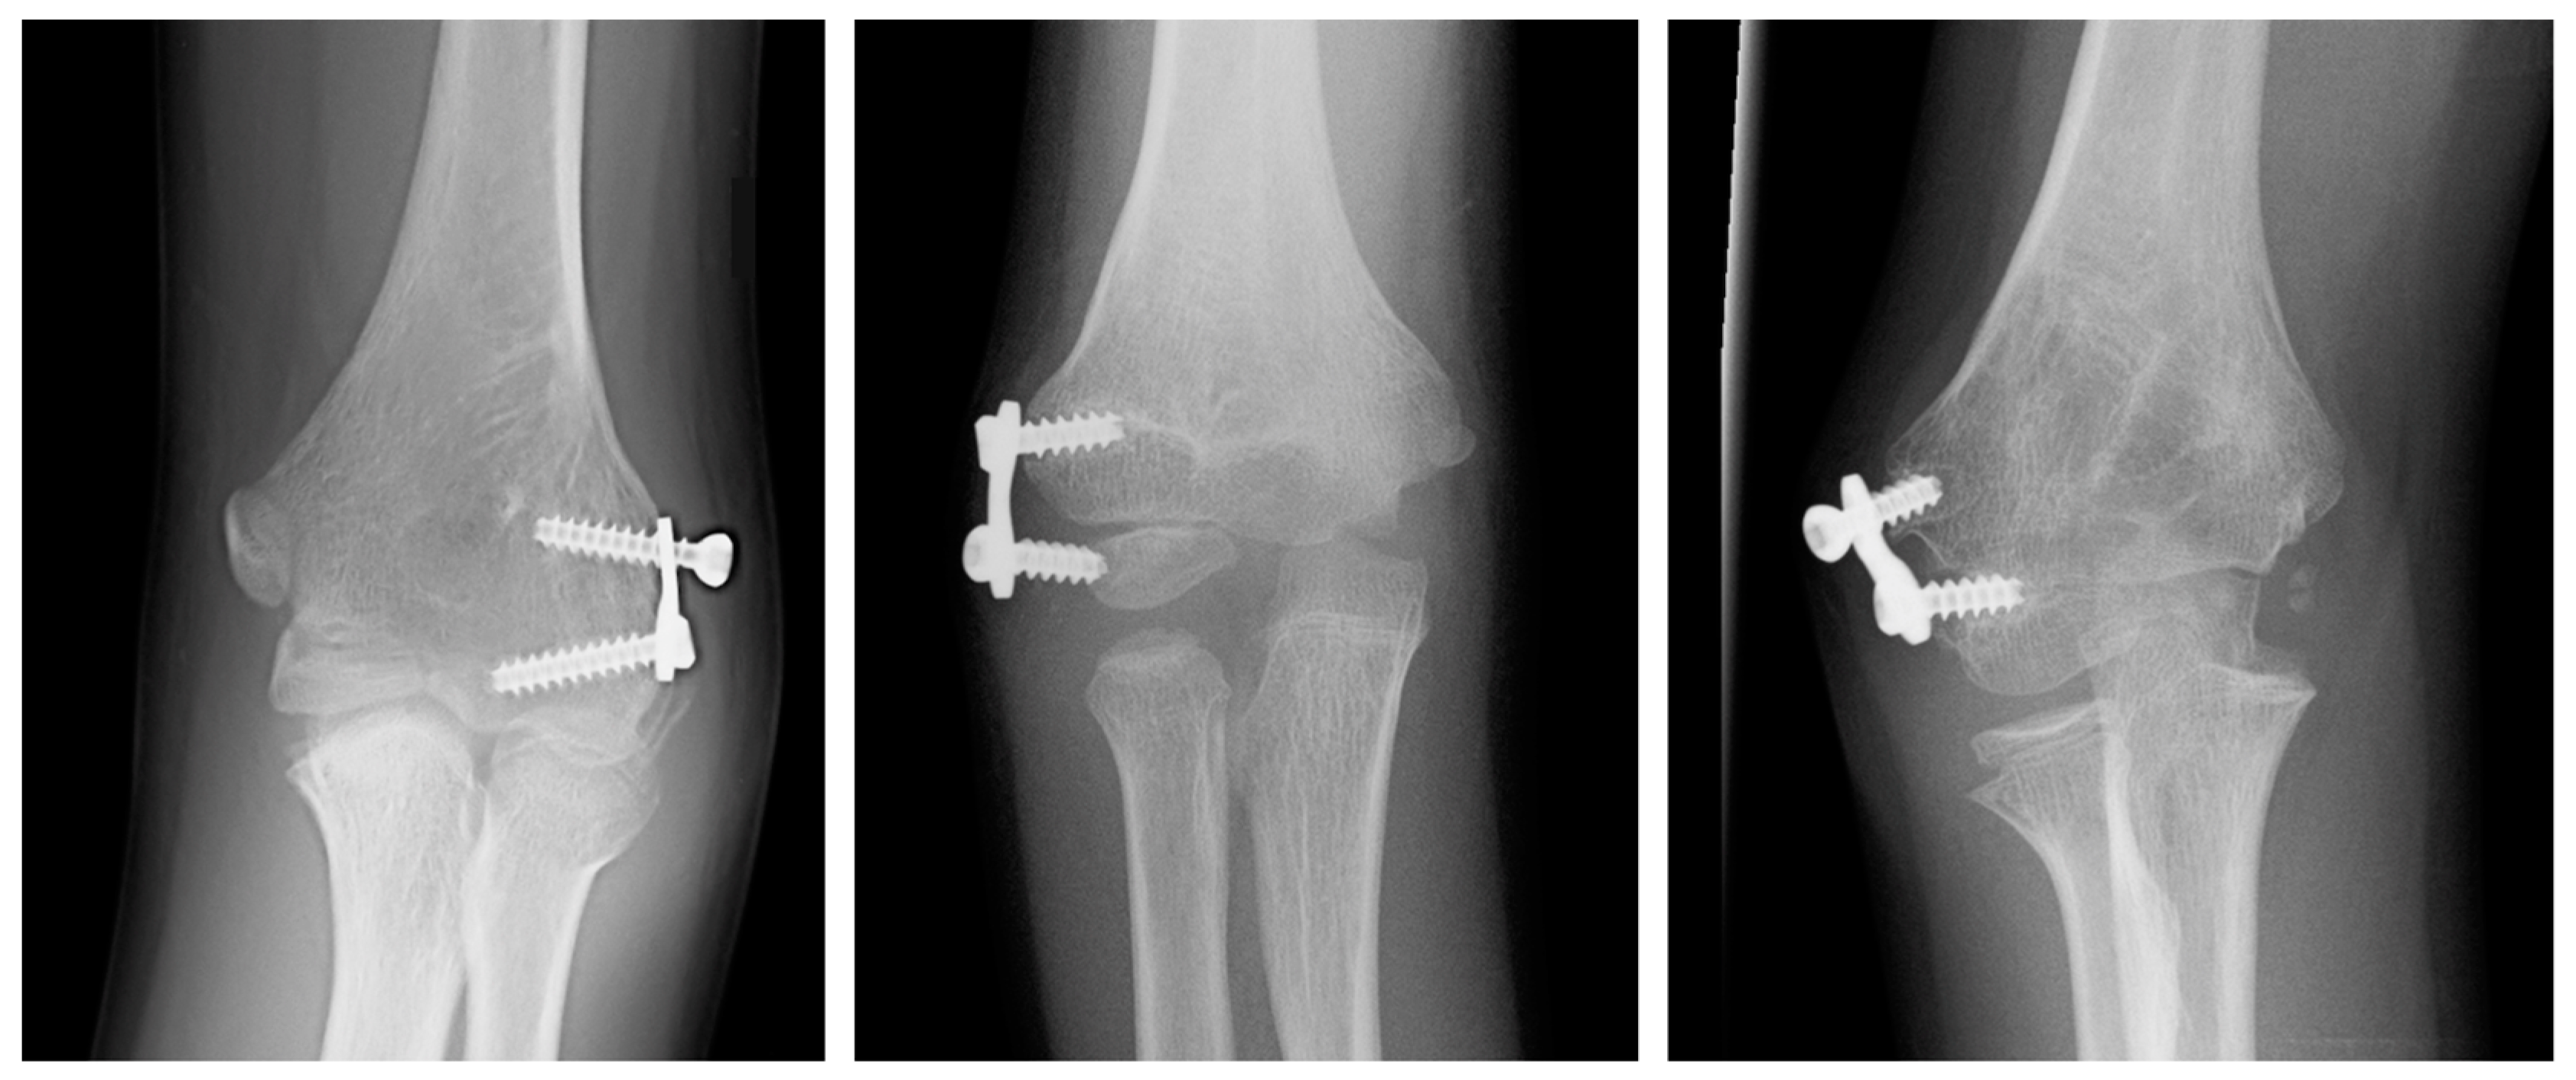

3.2. Comparative Pre- vs. Post-Analysis

| PRE | POST | Difference | p Value | |

|---|---|---|---|---|

| CA | −20 (−18 to −26) | −6 (−4 to −9) | −16 (−18 to −9) | <0.001 |

| HUA | −19 (−15 to −29) | −8 (−1 to −10) | −16 (−19 to −12) | <0.001 |

| BA | 90 (87 to 100) | 81 (76 to 83) | −11 (−17 to −7) | <0.001 |

| SCA | 29.8 (24.3 to 36.2) | 38.5 (38.1 to 40) | 7.5 (3.3 to 13.8) | <0.001 |

| LCHA | 61.6 (54 to 64.1) | 56.7 (54.6 to 57.3) | −4.8 (−6.8 to 0.6) | 0.018 |